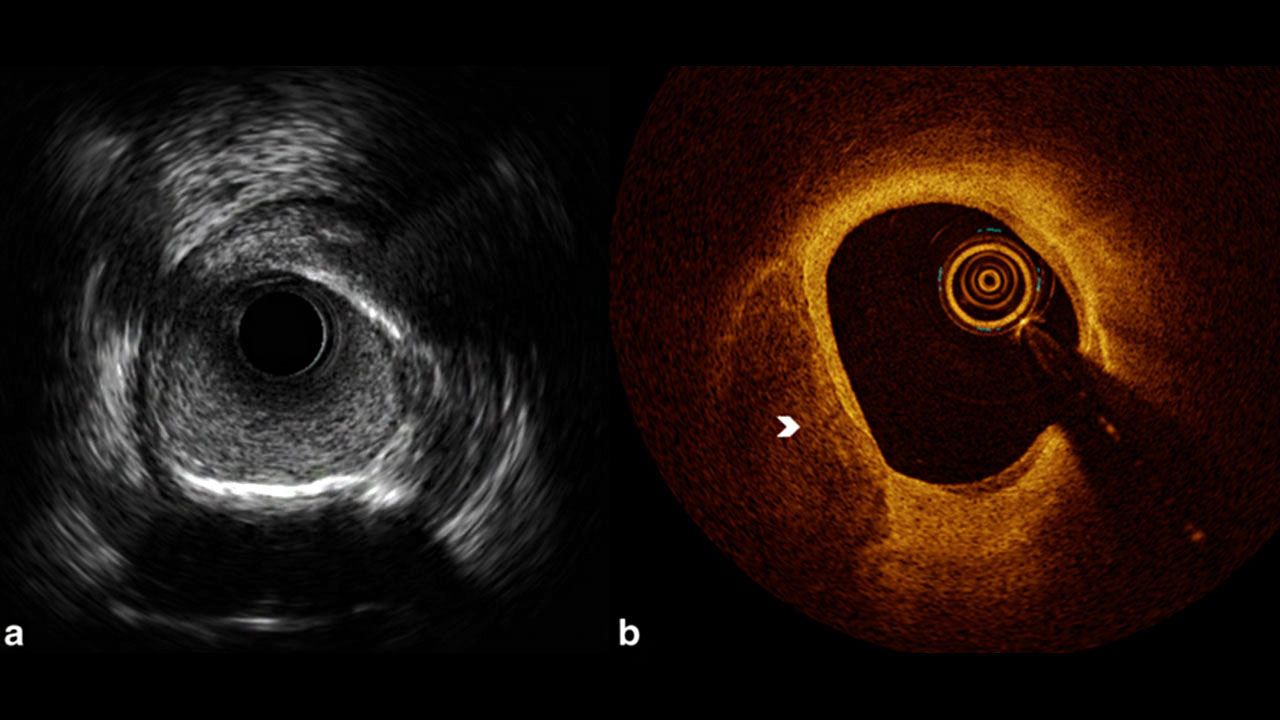

Optical coherence tomography (OCT) is an established intravascular imaging technique that uses light sources to capture inside of the coronary artery using very high resolution, 3D images from within the coronary artery lumen. Optical coherence tomography is based on typically employing near-infrared light. The use of relatively long wavelength light allows it to penetrate the contrast medium. This imaging technique is highly superior in assessing the minute details about the type of blockages, also about the stent properly apposed or not in the area of blockages.

Intravascular ultrasound (IVUS) is another intravascular imaging technique using a specially designed catheter with a mini ultrasound probe attached to the distal end of the catheter. The proximal end of the catheter is attached to computerized ultrasound equipment. It allows the application of ultrasound technology, such as a piezoelectric transducer or CMUT, to see from inside blood vessels out through the surrounding blood column, visualizing the endothelium (inner wall) of blood vessels in living individuals and good for sizing the vessel especially left main coronary artery for deploying accurate size stents or scaffords.